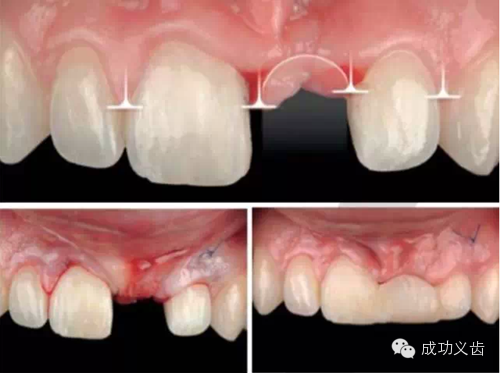

图11.又一例2颗下中切牙案例。

图12.神级的种植修复效果。2015年4月Dr.Ianki Gamborena 手把手向您传授他的秘密!

图21.软组织瓣怎么设计?怎么切?怎么缝?怎么玩转软组织,让种植体就像从牙龈中生长出来的一样?关键在于Predictable!